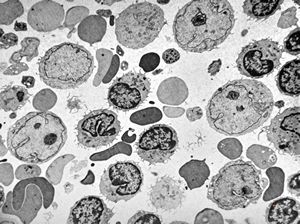

M, 1y. | gangliosidosis … bone marrow